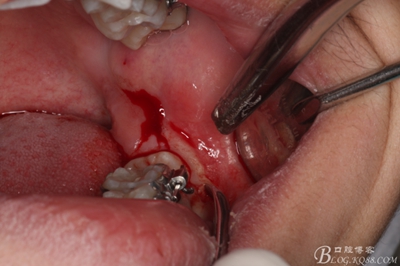

圖5.行遠(yuǎn)中水平切口+37近中垂直切口

圖6.兩個切口的交界處翻瓣

圖7.翻開粘骨膜瓣。

圖8。暴露出頰側(cè)骨壁,38完全位于骨內(nèi)